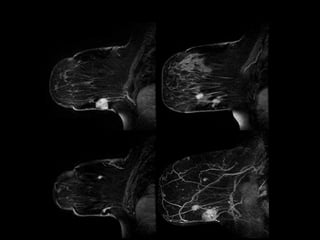

Pré-QTPré-QTPós-QTPós-QT